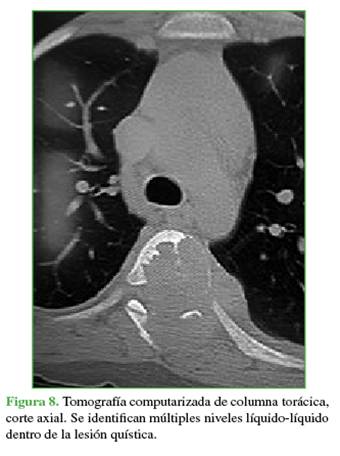

La zona afectada era 3-6, niveles III y IV de la clasificación de Weinstein-Boriani-Biagini.11 En los estudios complementarios, se observaron múltiples quistes tabicados con niveles líquido-líquido, por lo que se descartó un quiste óseo simple, de características expansivas y compresivas, ante este patrón se descartó la posibilidad de un hemangioma vertebral (Figuras 7 y 8). Este caso también se interpretó como una lesión secundaria a un QOA grado 3 de Enneking.13

El plan terapéutico consistió en descomprimir de manera urgente y estabilizar la columna vertebral, en un primer tiempo quirúrgico, y disminuir el riesgo de sangrado mediante una embolización selectiva, con un segundo tiempo de estabilización y artrodesis.